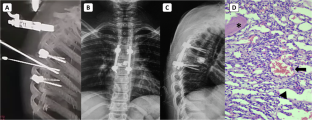

A 14-year-old boy presented with thoracic myelopathy signs. The MRI scan suggests T1 and T2 hyperintense signals within the T6 vertebral body with extramedullary extradural space occupying the lesion. The CT scan showed a “polka dot” appearance. Preoperative endovascular embolization followed by surgical decompression with posterior instrumented stabilization under O-arm navigation and tumor excision was planned. Cystic extradural lesion excised and vertebroplasty done at T6 level. Histopathology slides confirmed hemangioma.

The most common age of involvement is between 30 and 70 years it is rarely seen in the pediatric age group. To the best of our knowledge, fewer than 20 cases of pediatric aggressive vertebral hemangiomas have been reported. Based on a review of pediatric AVH only 4 patients have been treated with preoperative vascular embolization followed by surgical decompression and stabilization. O-arm navigated AVH excision and vertebroplasty has never been described in the literature; this being the first case. It also aids in the identification of tumor margins along with real-time monitoring of adequate resection.